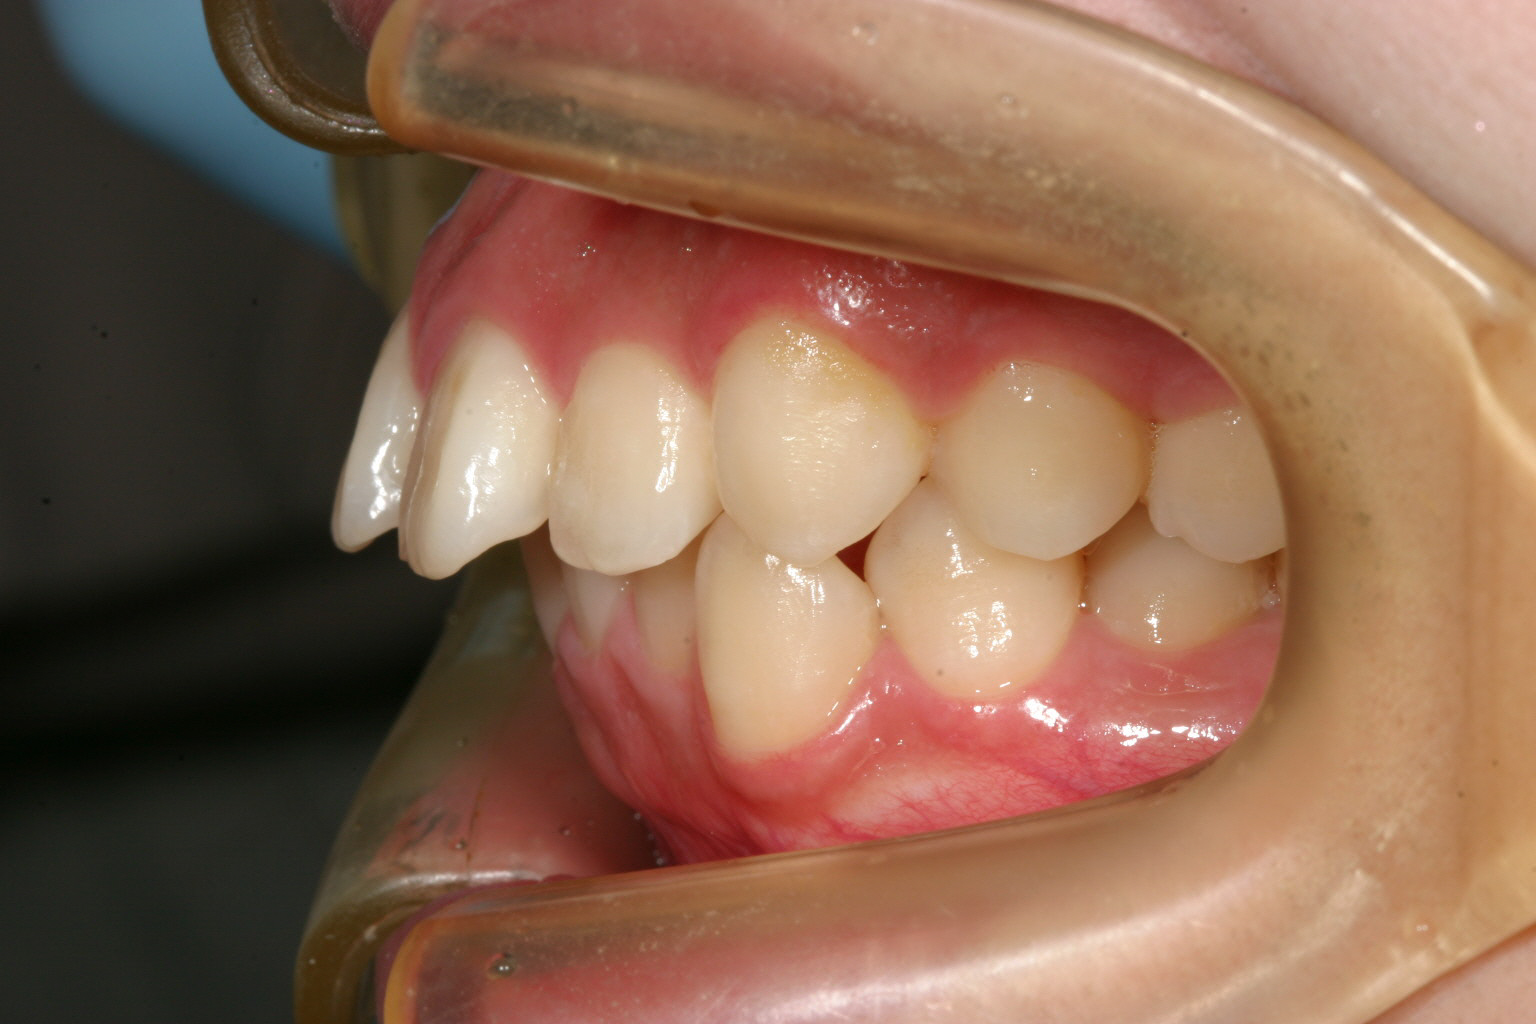

歯列がV字になっている為犬歯と犬歯の幅が狭く前歯が前に飛び出してます。

かなりの出っ歯ですね~

でっぱも改善出来ました。